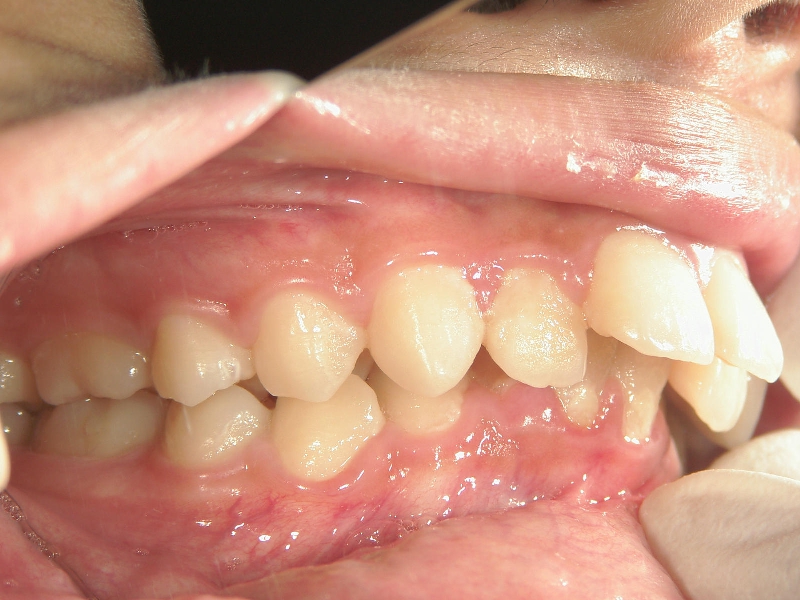

矯正歯科 治療前矯正歯科 治療前

矯正歯科 治療前 左右上下4番  計4本抜歯

no.18_2196_治療前_右.jpgno.18_2196_治療前_正面.jpgno.18_2196_治療前_左.jpg